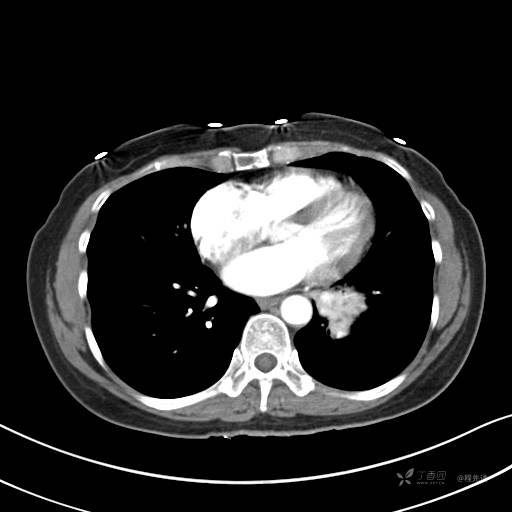

增强动脉期

动脉期CT值约74HU